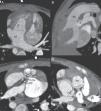

Os autores descrevem os achados em TC de uma criança do sexo masculino com 29 meses, referenciada para angio-TC cardíaca para avaliação de uma cardiopatia congénita complexa. O estudo foi efetuado em equipamento multi-corte de dupla-ampola de 128 cortes (Siemens Definition Flash) com sincronização electrocardiográfica prospetiva, que demonstrou mesocardia com situs inversus abdomino-auricular (Figura 1), discordância aurículo-ventricular e ventrículo-arterial com comunicação interventricular subpulmonar e artéria coronária única (Figura 2). A dose de radiação efetiva foi de 1,0mSv (DLP 25mGy*cm).

Mesocardia e situs inversus. (A) Topograma, (B) reconstrução multiplanar no plano coronal, (C) imagem axial do abdómen e (D) 3D volume rendering mostrando mesocardia, brônquio morfologicamente direito em posição esquerda, brônquio morfologicamente esquerdo em posição direita, fígado à esquerda, estômago e baço à direita e aorta anterior e direita e artéria pulmonar posterior e esquerda.

Ao: artéria aorta; B: baço; E: estômago; F: fígado; P: artéria pulmonar.